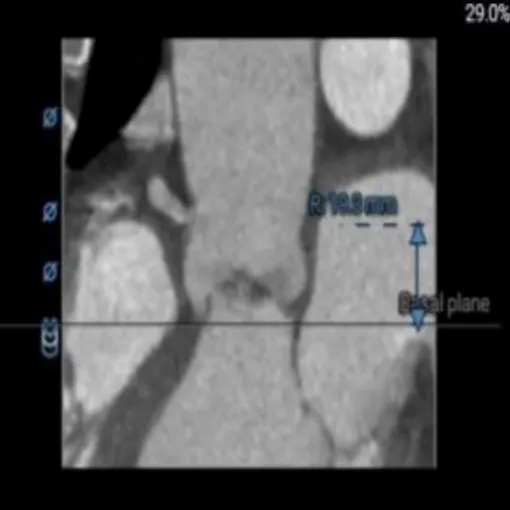

术前CT评估:功能性二叶瓣,左右融合嵴伴钙化,瓣叶增厚,瓣环径26.5,LVOT:28.7,瓣上可打开至23左右,窦部空间可,双侧冠脉开口高度可,主动脉弓大弯侧无明显钙化,双侧髂股动脉内径偏细,右侧股动脉分叉位于股骨头平面中部,左侧股动脉分叉位于股骨头平面中下1/3,建议右侧股动脉入路。

CT影像: